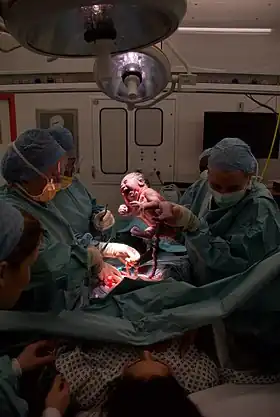

A team of five performing a caesarean section[1] | |

Caesarean section, also known as C-section or caesarean delivery, is the surgical procedure by which one or more babies are delivered through an incision in the mother's abdomen. It is often performed because vaginal delivery would put the mother or fetus at risk.[2] Reasons for the operation include obstructed labor, twin pregnancy, high blood pressure in the mother, breech birth, shoulder presentation, and problems with the placenta or umbilical cord.[2][3] A caesarean delivery may be performed based upon the shape of the mother's pelvis or history of a previous C-section.[2][3] A trial of vaginal birth after C-section may be possible.[2] The World Health Organization recommends that caesarean section be performed only when medically necessary.[3][4]

A C-section typically takes 45 minutes to an hour.[2] It may be done with a spinal block, where the woman is awake, or under general anesthesia.[2] A urinary catheter is used to drain the bladder, and the skin of the abdomen is then cleaned with an antiseptic.[2] An incision of about 15 cm (6 inches) is then typically made through the mother's lower abdomen.[2] The uterus is then opened with a second incision and the baby delivered.[2] The incisions are then stitched closed.[2] A woman can typically begin breastfeeding as soon as she is out of the operating room and awake.[5] Often, several days are required in the hospital to recover sufficiently to return home.[2]